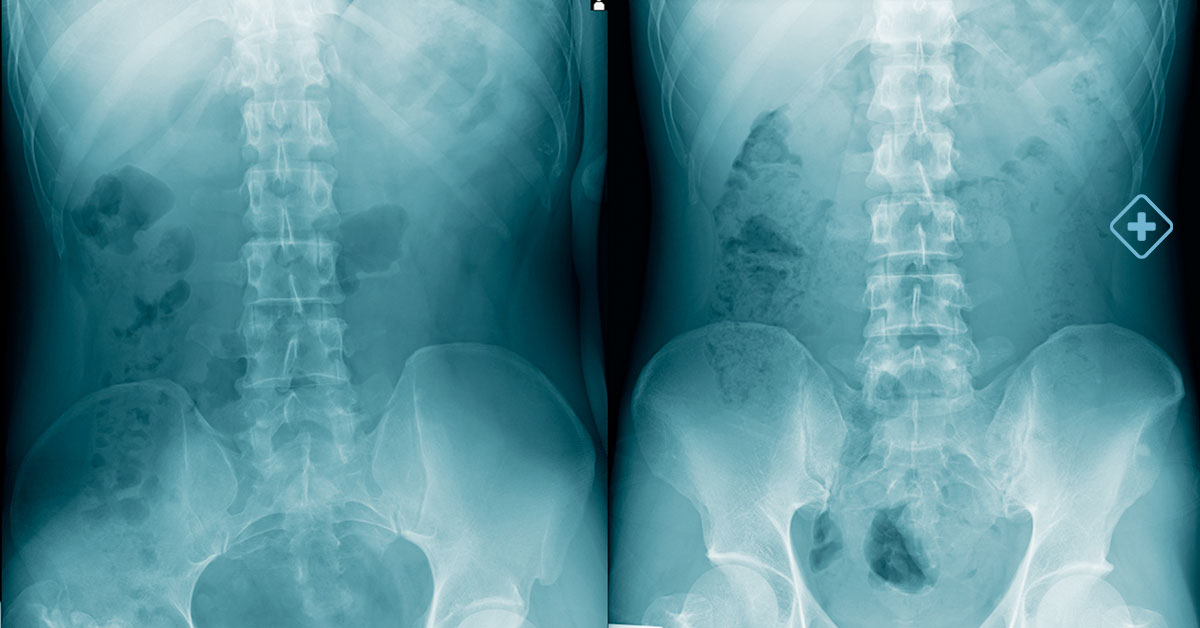

Esto puede incluir pruebas de diagnóstico avanzado, como resonancias magnéticas, tomografías computarizadas y radiografías, que ayudarán al médico a comprender completamente la naturaleza y la extensión del problema.